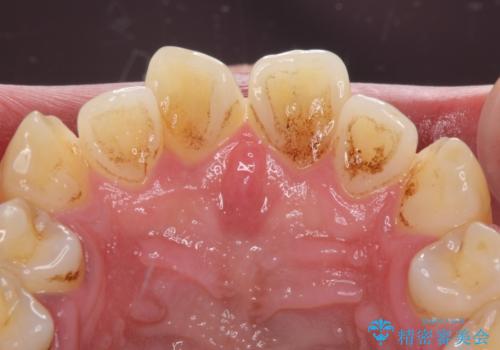

- 前歯が捻れており出っ歯であることを気にして来院された患者様です。

虫歯がほとんどなく、前歯以外にも歯列に問題があったため、歯列矯正を第一選択として強く勧めました。

しかし、時間をかけることは避けたいという強い要望があったため、セラミッククラウンによる補綴治療を行うこととしました。

補綴治療に先立ち、歯の形態を修正する必要があったため、残念ではありますが根管治療を行うこととしました。